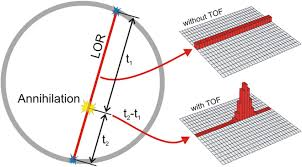

Each detector works together with the detector opposite to it – allows it to pick up on a line of response

What is a line of response?

When the photons from an annihilation reaction are emitted, they will travel in opposite directions of one another – makes a 180-degree line almost

How does a ‘dot’ from our image translate from the reaction at the PET detectors?

The detectors create a dot on our scanned image from the point at which the 2 photons are overlapping – or where they cross each other in the ring of detectors but we still need more information to specifically determine it!

What is needed in order for the PET detectors to determine where an annihilation reaction occurred on a line of response?

Requires multiple line of responses to figure out where the intersection of where the annihilation reaction took place

What is the new technology in PET that allows us to get an idea of where an annihilation event happened on the line of response?

Time of flight technology

What is time flight technology?

Where the new technology allows us to better determine where an annihilation event happened based on how soon (time) the photon hit the detector – i.e. it taking 0.5 seconds for the right side vs. 1.5 seconds for the left side → annihilation most likely happened more on the right

How does time flight technology affect how our images on PET turn out?

It decreases our need for having multiple line of responses – able to use shorter line of responses and get rid of all the bad and excess information that makes the images less clear – better able to focus on what we intend to image

How does time flight technology affect how we dose and image the patient in PET?

If we’re able to eliminate bad information using the new technology, we won’t need to overcome the bad information with good information – able to give less of a big dose and not need to image as long